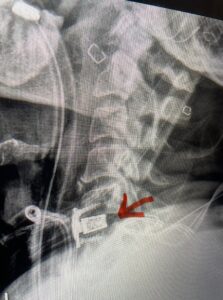

Fig 5a: Sagittal and axial cervical fine-cut CT scan demonstrating severe osteophyte formation causing cord compression at C 56 (red arrow)

Fig 5b: Sagittal and axial cervical fine-cut CT scan demonstrating severe osteophyte formation causing cord compression at C 56 (red arrow)